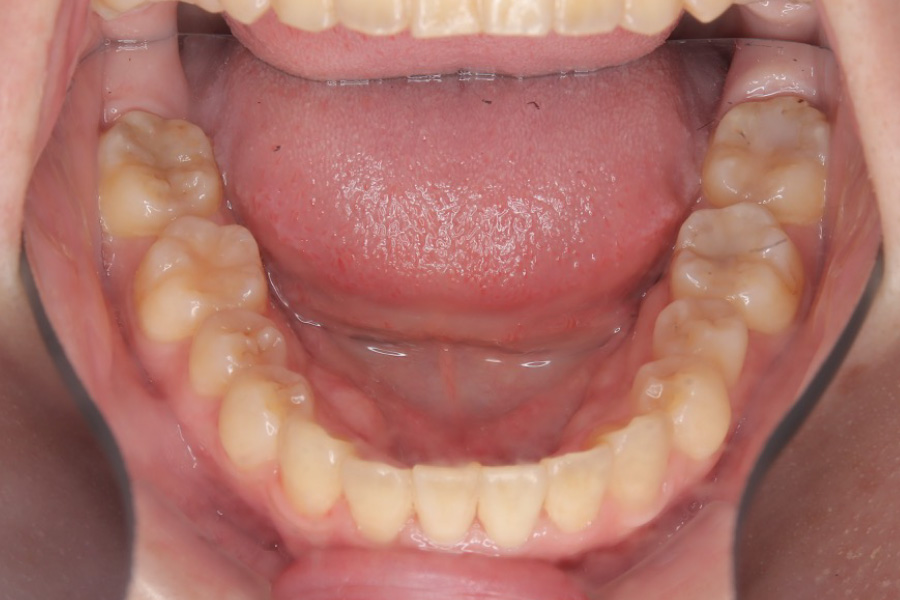

治療後

主訴 全体のガタつきが気になる

治療内容 インビザライン矯正

非抜歯

治療に伴うリスク 矯正終了後は、リテーナーを指示通りに使用し、歯の後戻りを防ぐ必要があります。